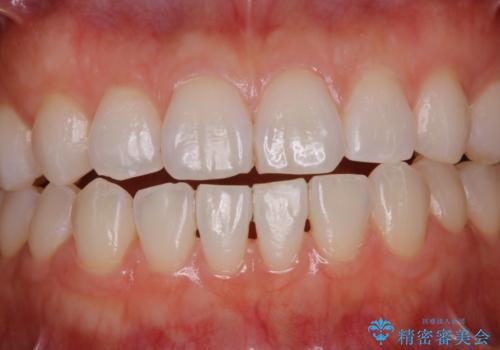

PMTCで見た目を綺麗に

- 専門的な機械ででしっかりとキレイにクリーニングしてほしいとのことでしたPMTC60分コースを行いました。

PMTCは、歯に付着した汚れを除去していくため、着色が気になる場合にも行うことができます。ご自身でのセルフケアだけで着色を落とそうとすると、逆に歯を傷つけてしまったり、精密に汚れを除去できないこともあります。また、日常生活で着色しやすい飲食物を避けたりすることはストレスに感じてしまったり、あまり現実的ではありません。

毎日丁寧に歯磨きをしていても、日常生活での飲食物などにより着色してしまうことはあります。PMTCでは、歯の表面の凸凹にミネラルを補給して、ツルツルの表面に仕上げます